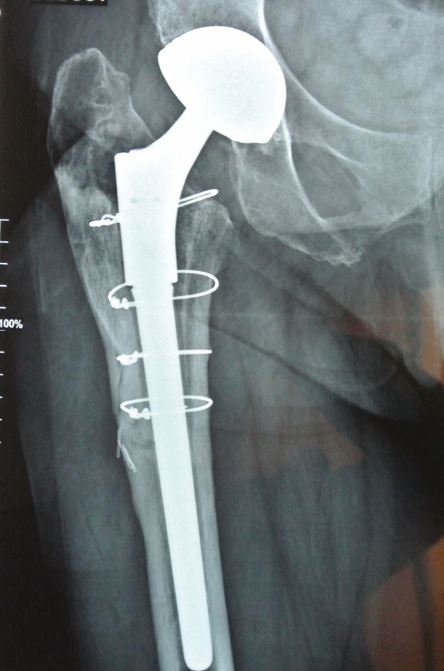

Case report n°2 (Figure 2)

PPF at the cementless pivot (Vancouver B2) after acetabulum-only revision

Femur-only revision: cementless monoblock long stem Locking stem, fracture repair with cerclage wiring.